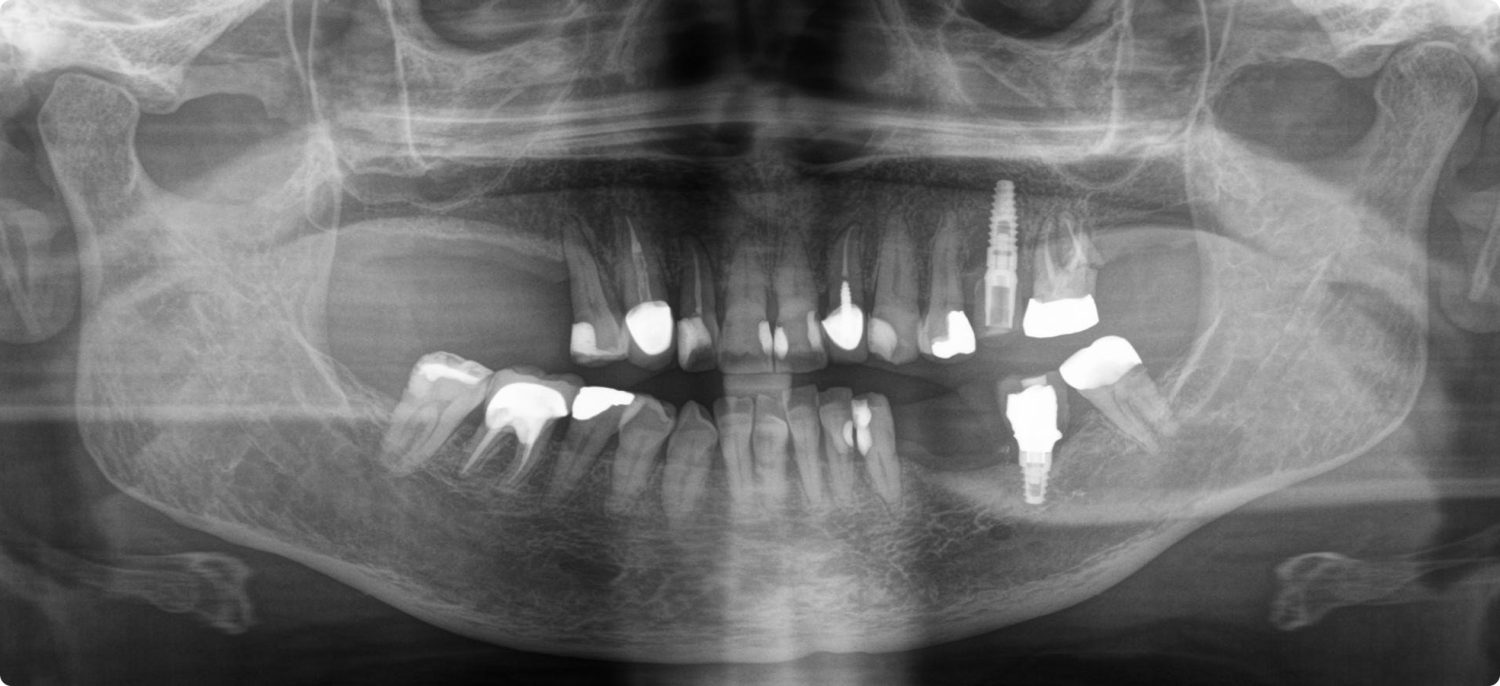

Ms Elizabeth Qashou, a 64-year-old executive PA from Prestwich, Manchester, has been awarded £10,000 from a former dentist with the help of specialist dental negligence solicitors the Dental Law Partnership after dental errors dating as far back as 2007 led to years of discomfort and anxiety after her severe periodontal disease went untreated.

However, despite years of regular appointments and treatments, in August 2020 after attending the practice due to pain in a tooth, Ms Qashou was surprised to be told by Dr Marques that she had significant bone loss, which was a symptom of advanced periodontal disease. “It was extremely upsetting and a big shock to find out about my periodontal disease at such a late stage – especially as I had swapped to paying privately for my dental treatment.”

“After the bone loss came to light, I changed to a new practice and was also diagnosed with decay at a number of teeth that would likely require extraction, as well as being told I needed replacement fillings and a replacement crown,” Ms Qashou recalled.

Frustrated with the experiences she had gone through, Ms Qashou contacted the Dental Law Partnership in 2019. Further analysis revealed numerous errors dating as far back as 2007, including periodontal disease being left to progress untreated, which had led to the tooth extractions and could have been avoided. Furthermore, poor crown fittings and fillings had led decay to progress, resulting in further  extractions in the future.